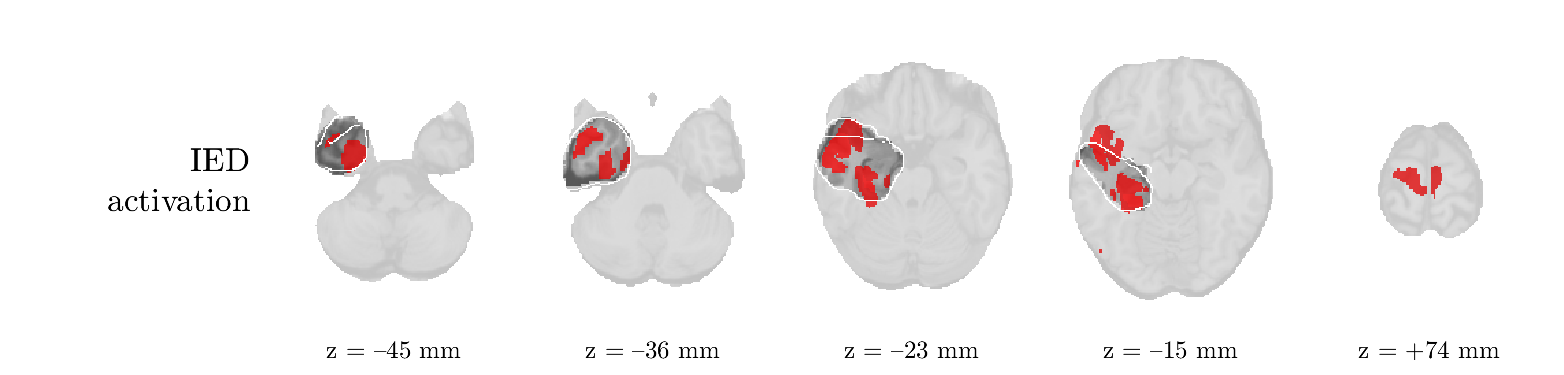

We analyze the solution with sources. Figure 1 shows the EEG signatures and HRF waveforms. One of the sources is highly correlated to the MWF reference (in grey), which was already known from Table B.3. This IED-related source had a typical low-frequency spectrum, which is expected for the typical spike-and-wave interictal discharges. The topography is relatively diffuse, although the highest amplitudes are mostly in the left hemisphere. This is in accordance with the lateralization of ictal onset zone (left temporal lobe, cfr. Table 1). There are some noteworthy observations to be made about some of the other components. The fourth has an unusually sharp spectrum, is mainly localized on two nonadjacent center electrodes, and is sustained for a single period of many seconds Hence, this component likely captured an artifact (of yet unknown origin), although we spotted no large-amplitude changes in the EEG itself. Similarly, the third source is only present at one frontal electrode, and exists in a frequency range above 20 Hz. It might represent a muscle artifact, e.g., due to frowning or twitching of some muscles in the forehead. The HRFs of all ROIs are shown in Figure 1(b). Two of the basis functions seem to have converged to a very similar waveform, which is an unfortunate possibility if two initial HRFs are too close to the same local optimum in their respective parameters. This reduces the expressive power of the basis set, which is clearly visible, since many ROIs have a nearly identical HRF. One of the twenty ROIs with the highest-entropy HRF overlapped the IOZ, although clearly this HRF (bold line) is not among the most dissimilar waveforms for this patient. This is also visible in Figure 2: both the HRF entropy and extremity maps show a small overlap with the delineated IOZ. Despite the good correspondence in the EEG domain, no significant (de)activation of the IED-component is found inside the IOZ.